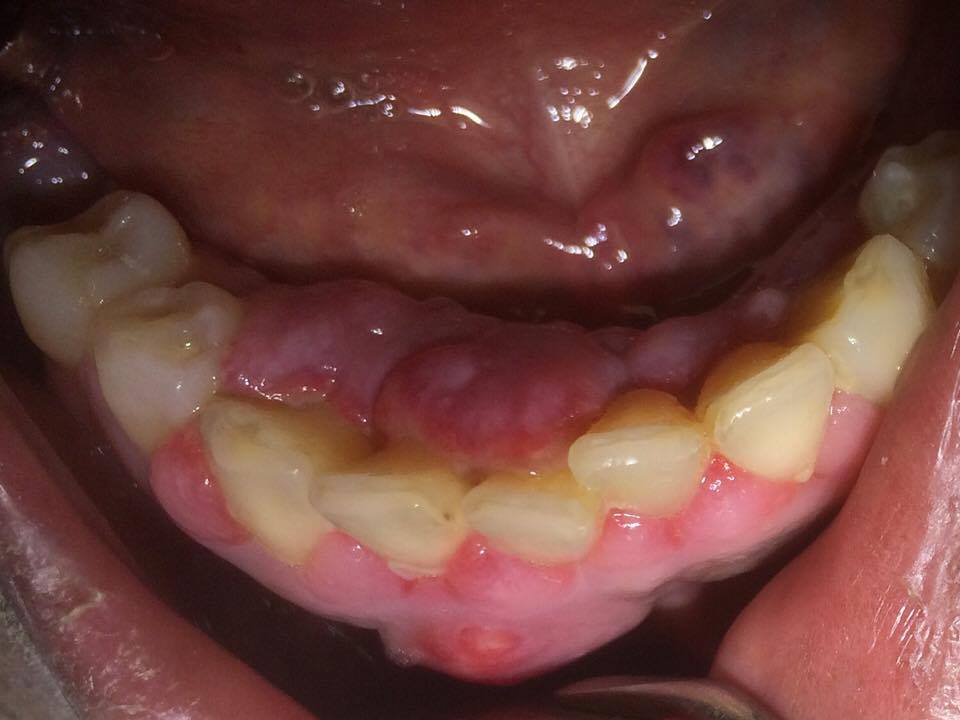

Patiente 47 ans d'origine africaine est adressé par son médecin traitant pour une hyperplasie gingivale en secteur antérieur mandibulaire.

Je pense à une hyperplasie gingivale d'origine médicamenteuse (inhibiteur calcique) sur facteurs locaux aggravants (mauvaise HBD, maladie parodontale chronique)

Au rdv de réévaluation, l'hypertrophie gingivale s'est nettement résorbée. La thérapeutique est favorable.

La patiente a été adressée à un omni pour TE des dents nécrosées causales (42-41-31) et thérapeutique initiale parodontale.